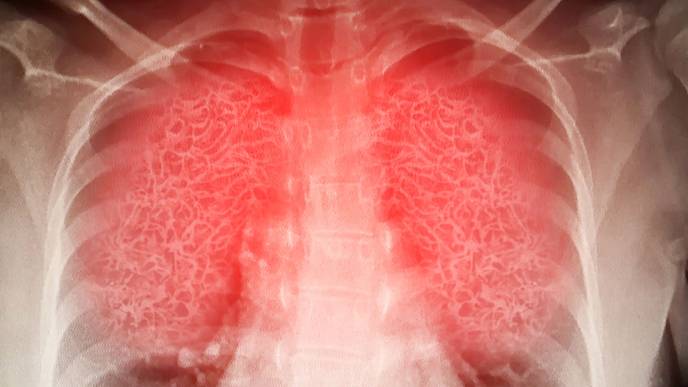

A recent USC study provides new information about why SARS-CoV-2, the virus behind the COVID-19 pandemic, may elicit mild symptoms at first but then, for a subset of patients, turn potentially fatal a week or so after infection. The researchers showed that distinct stages of illness correspond with the coronavirus acting differently in two different populations of cells.

The team found that when SARS-CoV-2 infects its first-phase targets, cells in the lining of the lung, two viral proteins circulate within those cells — one that works to activate the immune system and a second that, paradoxically, blocks that signal, resulting in little or no inflammation. The team also discovered a second pathway the virus sometimes takes, for entering immune cells. This alternative pathway both stunts the virus’s ability to reproduce and prevents production of the second, immune signal-braking protein. The first protein is then able to spur rampant inflammation linked to severe symptoms.